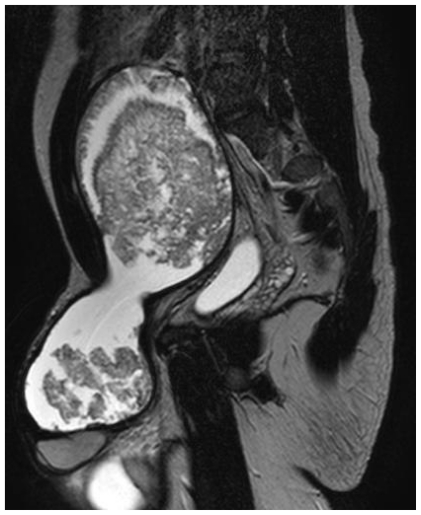

Figure 1.

24 Year old male with large hemorrhagic abdominolscrotal hydrocele: TSE T2-weighted sagittal plane. The caudal-cranial mass (about 23 cm) extends in the abdomen through the right inguinal canal to the top of L5. Since the mass can not expand in the right inguinal ring, on this view the lesion appears "hourglass" shaped. Posteriorly to the mass it is possible to recognize the bladder (i.e.: hyperintense structure). Just below the mass on the right side, there is a hydrocele with fluid signal intensity.